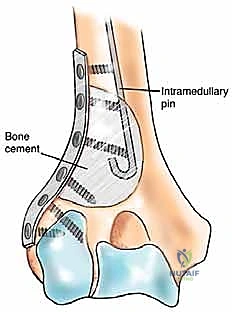

3. الاستئصال الجذري والمفاصل الصناعية الخاصة بالأورام (Tumor Endoprosthesis)

في حالات التدمير الواسع جداً للعضد القريب (قرب الكتف) أو العضد البعيد (قرب الكوع)، أو في حالة النقيلة الوحيدة التي تتطلب استئصالاً جذرياً (En-bloc resection) لضمان عدم عودة الورم:

* يقوم الدكتور محمد هطيف باستئصال الجزء المصاب من العظم بالكامل مع الورم المغلف به ككتلة واحدة، بهوامش أمان سليمة.

* يتم استبدال العظم والمفصل المستأصل بـ مفصل صناعي ضخم خاص بالأورام (Modular Megaprosthesis). هذه المفاصل مصنوعة من التيتانيوم والمعادن المتقدمة، وتأتي بقطع قابلة للتركيب لتناسب الطول الدقيق للعظم المفقود.

* هذه الجراحة تتطلب مهارة فنية عالية جداً لإعادة خياطة العضلات والأوتار (مثل أوتار الكفة المدورة في الكتف) في المفصل الصناعي لضمان عودة حركة الذراع.